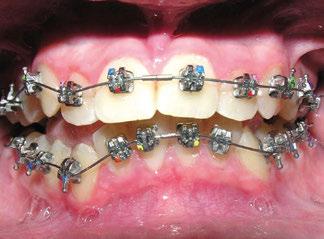

Tras la terminación de la fase ortopédica, se continuó con la colocación de los brackets

mencionados anteriormente. La prescripción de estos fue de alto torque en los incisivos superiores y en los cuatro caninos, y de bajo en los incisivos inferiores. Tras 12 meses desde la colocación de los brackets y una vez conseguida la normalización de las relaciones oclusales, se colocaron unos retenedores fijos de canino a canino en ambas arcadas de acero trenzado de 6 hilos (.017” superior y .019” inferior) y un guarda de contención nocturna hasta la terminación del crecimiento puberal.

Con el cementado de los brackets de la técnica Universal Smile System

(USS), como se aprecia en las figuras 23 a 25, comienza la segunda fase de tratamiento. Esta duró tan solo 12 meses debido a que gran parte de las relaciones oclusales habían mejorado durante la etapa anterior. Los resultados finales del tratamiento se observan en las figuras 26 a 30 , con la corrección de la clase molar y canina, el resalte y la sobremordida, el centrado de las líneas 1/2 y la curva de Spee. La mejoría en la macro, mini y microestética facial se aprecia en las figuras 31 a 33 , a pesar de la evidente desviación del mentón hacia

La segunda fase de tratamiento, con aparatología fija, se realizó con brackets de autoligado pasivo de la técnica USS (Universal Smile System). Se colocaron brackets con prescripción de alto torque en los caninos superiores (+11 º) e inferiores (+13 º) para ayudar al desarrollo transversal de las arcadas, así como para provocar un movimiento radículo-lingual de estos para mejorar la posición de sus raíces. Alto torque en los incisivos centrales (+22º) y laterales (+13 º) superiores para compensar el efecto de linguoversión

que producen los elásticos intermaxilares de Clase II, así como bajo torque en los incisivos inferiores (-11 º) para minimizar la protrusión producida por estos mismos elásticos y por el anclaje recíproco debido al apiñamiento dentario (10-12).